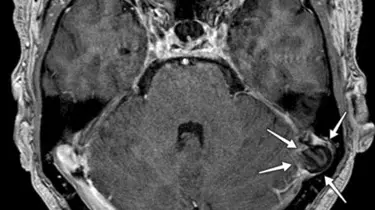

Ortopædkirurgi Lars Blønd har for nyligt udviklet en ny og vellykket operationsteknik til behandling af Artroscopisk Trokleoplastik, der udføres med en kikkertoperation.